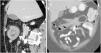

Computed tomography. A) Transverse view of intestinal intussusception; a “target” or “doughnut” image can be seen (arrow) with a lipoma in its centre, as well as mesenteric vessels and fat in the periphery (arrowhead). B) Longitudinal view of the intussusception; the colon can be seen with thickened walls and mesenteric fat and vessels entering the intussusception.

We describe the case of a 56-year-old female with a history of obesity, multinodular goiter and fibromyalgia. She went to the Accident and Emergency department complaining of right abdominal pain and haematochezia; she had no changes in bowel habit, weight loss, anorexia or fever. Blood analysis showed mild anaemia (Hb 11.3 g/dl); other parameters were normal. Colonoscopy revealed a pedunculated polypoid lesion about 5 cm in diameter in the hepatic flexure, with no clear glandular pattern and ulcerated areas oozing blood on the surface, causing almost complete stricture of the lumen of the colon (Fig. 1). Despite having active bleeding, management was conservative due to the small amount and diffuse nature. The colonoscopy was completed with no other findings; biopsies were taken from the non-bleeding areas of the lesion, the histology of which revealed focal hyperplastic changes. As malignancy was suspected and the patient had persistent bleeding (even though of small amounts), an abdominal computed tomography (CT) scan was performed, which showed a rounded image with concentric rings of different densities (sagittal sections) and an image of the colon within the colon (in the coronal sections), findings compatible with colocolic intussusception caused by a mass with lipomatous characteristics, without signs of intestinal obstruction or distension of loops (Fig. 2). In view of these findings, we decided to perform an extended right hemicolectomy with ileocolic anastomosis. Pathology examination of the surgical specimen confirmed the diagnosis of a 55 × 43 mm submucosal lipoma, with mucosal ulcerations and erosions. There was no evidence of dysplasia or carcinoma in the surgical specimen, or pathological lymphadenopathy. At the postoperative check-up, the patient was asymptomatic, with normal intestinal transit and no complications.

Intestinal intussusception is the introduction of a proximal segment of the intestine into a more distal segment; it represents only 1–5% of intestinal obstructions and can be caused by malignancy (lymphoma, adenocarcinoma) or have a benign cause, such as intraluminal lipomas. The diagnosis of intussusception is confirmed by imaging tests, with CT being the most sensitive and specific (83–100%). The characteristic finding is the presence of colon within colon or ileum within colon, as was found in the case we present here. CT will also show the existence of proximal occlusion and any distension of intestinal loops.3,4